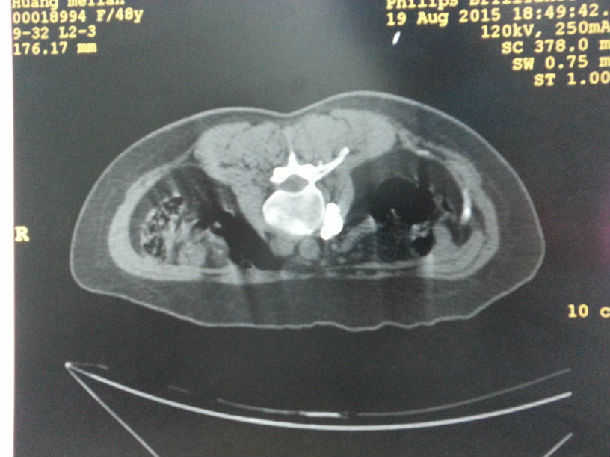

腰交感神经化学毁损术是一项通过使用医用酒精毁损部分腰交感神经组织,从而阻断其神经传导功能的微创介入治疗手段。手术在CT引导下,使用一根直径仅0.7mm的穿刺针,到达L2椎体前外侧的交感神经节处,注射造影剂,显示位置确切后,注射75%医用酒精15ml对腰交感神经进行毁损,通过损毁部分交感神经节后纤维,使交感神经兴奋性降低,不仅增加腰部动、静脉的血流量,使神经根缺血得到改善,还使其支配的下肢血管扩张,侧支循环建立,使下肢整体的血液循环得到改善,从而治疗因腰部及下肢缺血而引起的疾病。手术效果确切,起效快,时间短,无不良反应及后遗症,术后即可从事日常生活及工作。

下位手术中CT影响及术前术后下肢血运情况。